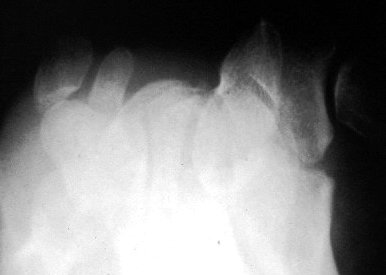

Carpal tunnel Xray view

• Trapezium fracture